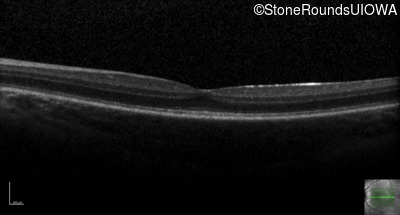

The clinical features supporting the diagnosis of incomplete achromatopsia in this patient include: nystagmus noticed in the first year of life; reduced acuity, poor color vision, a normal fundus appearance, a normal OCT, normally sighted parents and absence of a similarly affected male elsewhere in his mother's family.